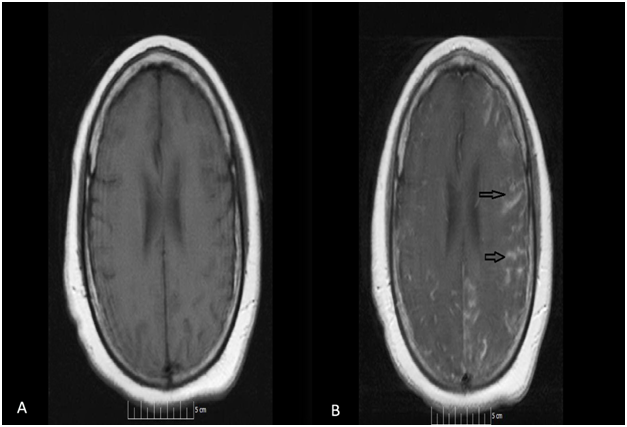

52-year-old African American female presented to our facility with altered mental status. Her past medical history was significant for Neurosarcoidosis, Diabetes Mellitus, Epilepsy and Hypertension. She was febrile with a temperature of 101.6F and mildly tachycardic to 103 beats per minute. Neurological examination revealed a divergent strabismus, a nonreactive right pupil, with no nuchal rigidity. Serum hematology and biochemistry was non-contributory. Urinalysis showed pyuria and bacteriuria. Chest x-ray showed increased interstitial markings prominent in the perihilar regions. Magnetic resonance imaging(MRI) of the brain with gadolinium showed post contrast diffuse leptomeningeal enhancement on T1 images (Figure 1, panel A & B), and there was a nodular pattern of leptomeningeal enhancement consistent with acute neurosarcoidosis (Figure 2). Lumbar puncture was unsuccessful due to body habitus. A preliminary diagnosis of urinary tract infection was formulated and broad spectrum antibiotics were instituted. Corticosteroids could not be administered as the patient was in severe sepsis.

Figure 1 Magnetic resonance imaging (MRI) of the brain with gadolinium contrast showing post contrast diffuse leptomeningeal enhancement on T1 images (Figure 1, panel A & B- arrows).